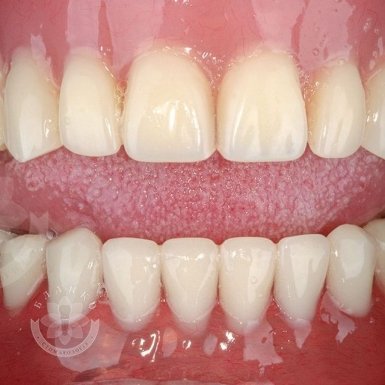

Зубна імплантація — це сучасне та надійне рішення для відновлення втрачених зубів. У стоматологічній клініці Бланко ми пропонуємо імплантацію зубів «під ключ», що означає повний комплекс послуг — від діагностики до встановлення коронки, без прихованих платежів та несподіваних витрат.